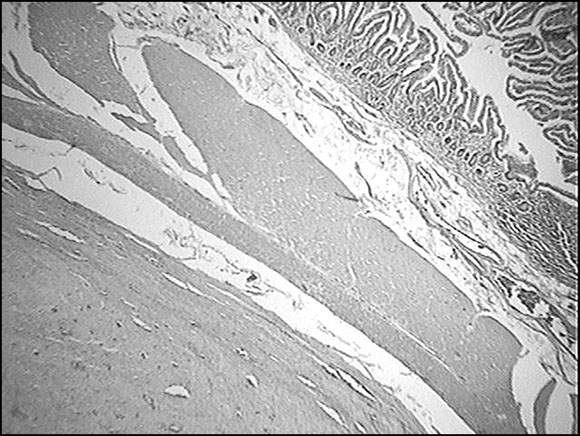

Figura 1: Coloración con Tricrómico de Gomori. Biopsia del tumor.

Figura 3: Histología del tumor estromal